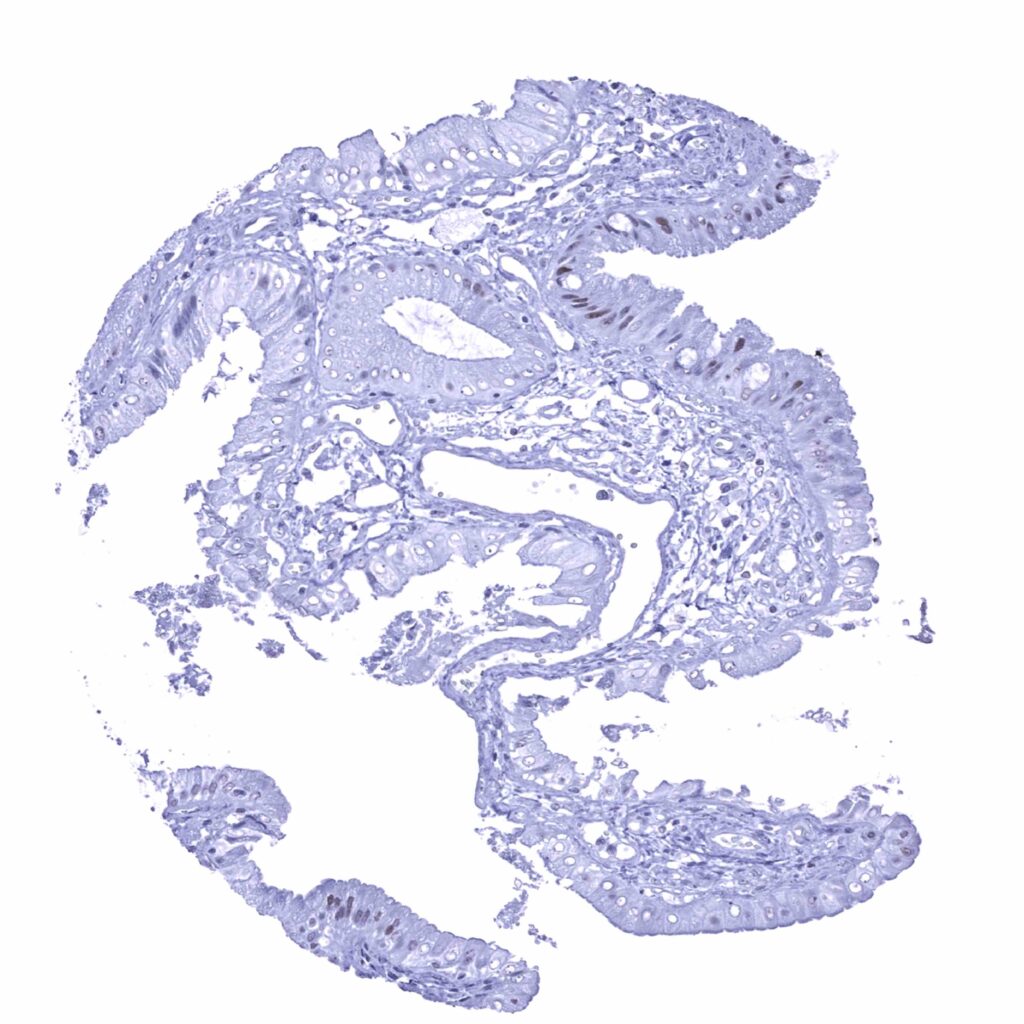

Appendix, mucosa – Weak nuclear p53 positivity of some epithelial cells at the base of crypts (p53 immunohistochemistry)